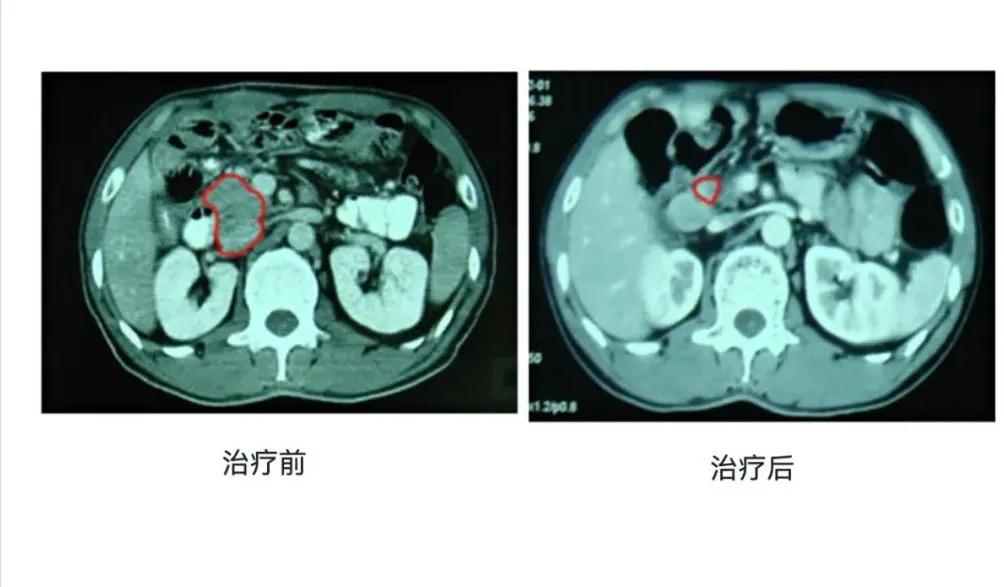

仅用了三个星期,治疗就结束了,姜福生在2002新年前夕出院,回到了老家。年后,姜福生到北京复查,CT结果显示:肿块消失。那一刻,姜福生的妻子喜极而泣,哭出了被告知丈夫得癌,生命所剩无几时的绝望,哭出了陪伴丈夫治疗时的艰辛,哭出了得知丈夫劫后余生的狂喜!此后,姜福生定期复查,他的病历档案中净是令人心安和欣慰的记录:

2004年10月3日(治疗后36个月)无症状,胰头肿块消失;